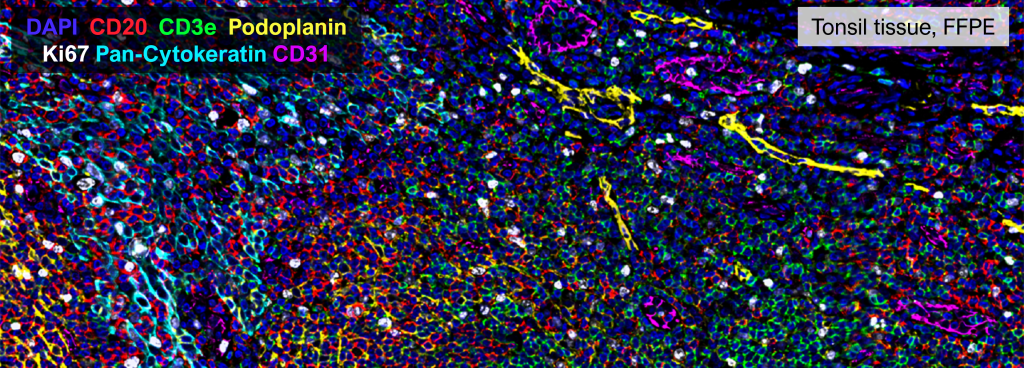

CO-Detection by indexing (CODEX) technology (PhenoCycler) allows for highly-multiplexed immunofluorescence (40+ markers) on formalin-fixed paraffin embedded (FFPE) or fresh frozen tissues. Thus, this system offers a high-dimensional cellular analytic platform that can capture tissue architecture with pertinent cellular components and phenotypic changes at a single cell resolution.

These highly specific antibody-reporter pairings allow for the visualization of more than 40 proteins of interest (“markers”) within the same tissue section (FFPE or fresh frozen).